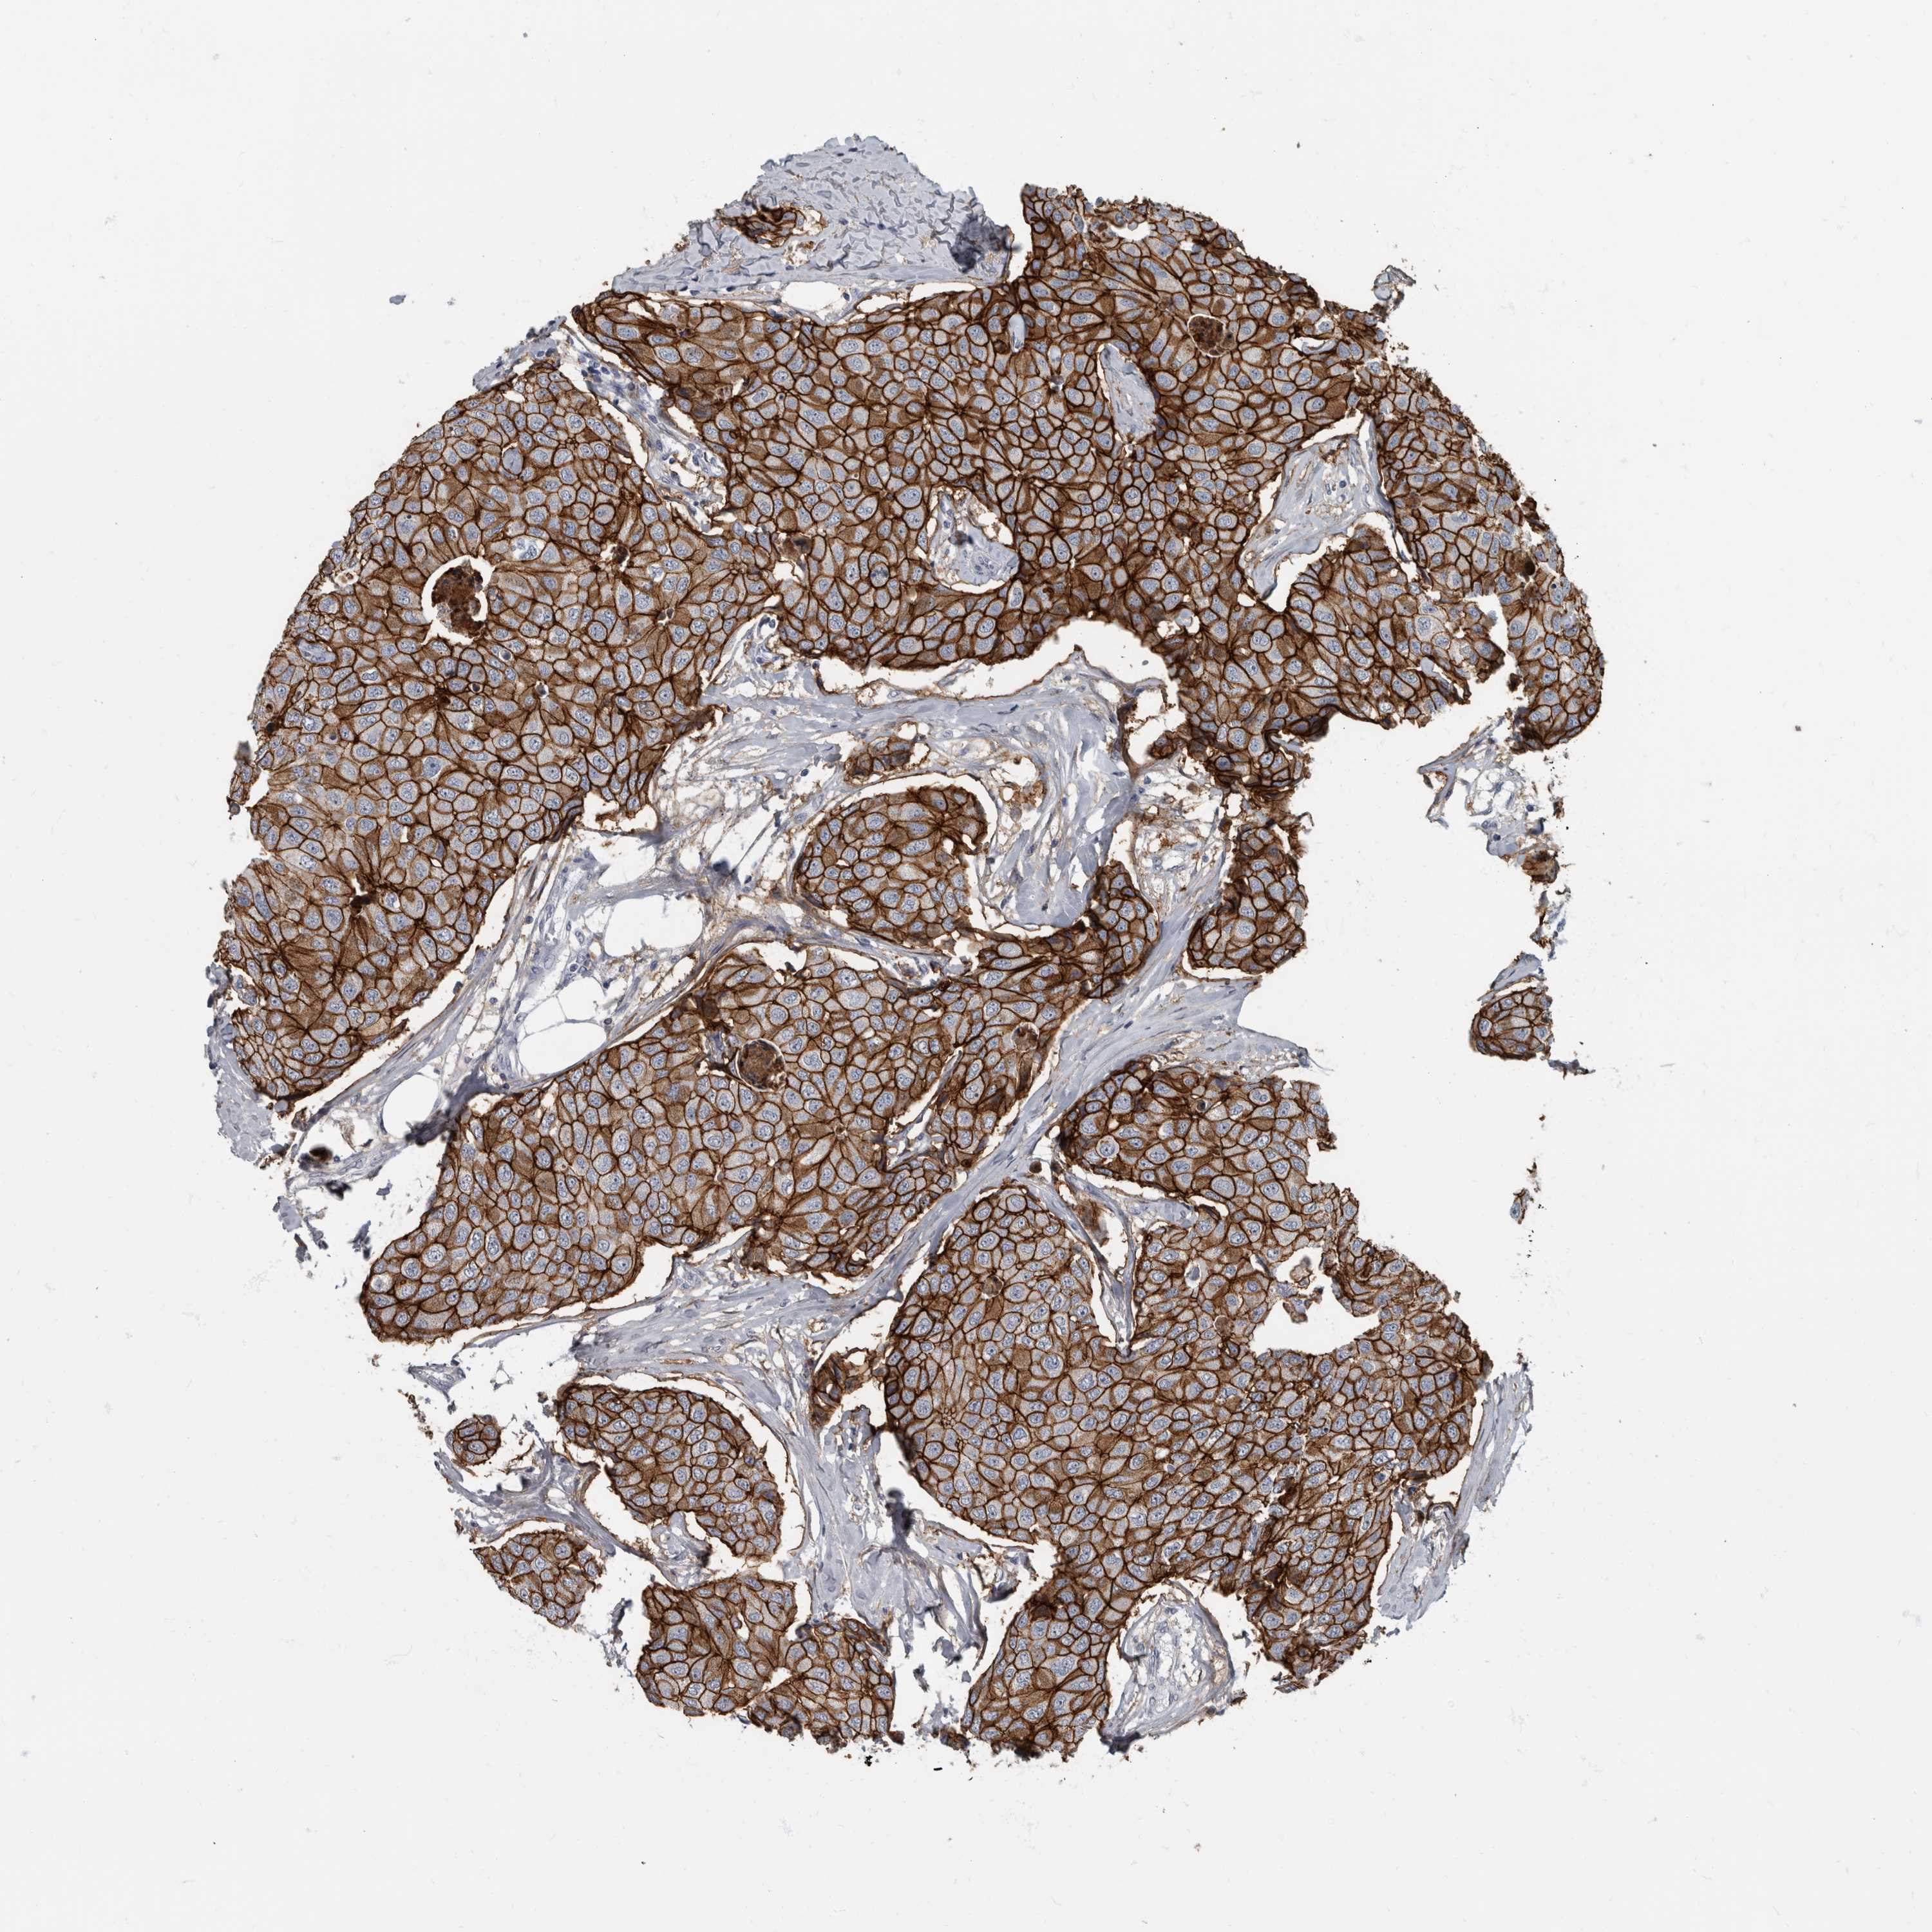

CANCER BREAST CANCER Show tissue menu

BRCA TCGA BRCA VALIDATION PROTEIN EXPRESSION